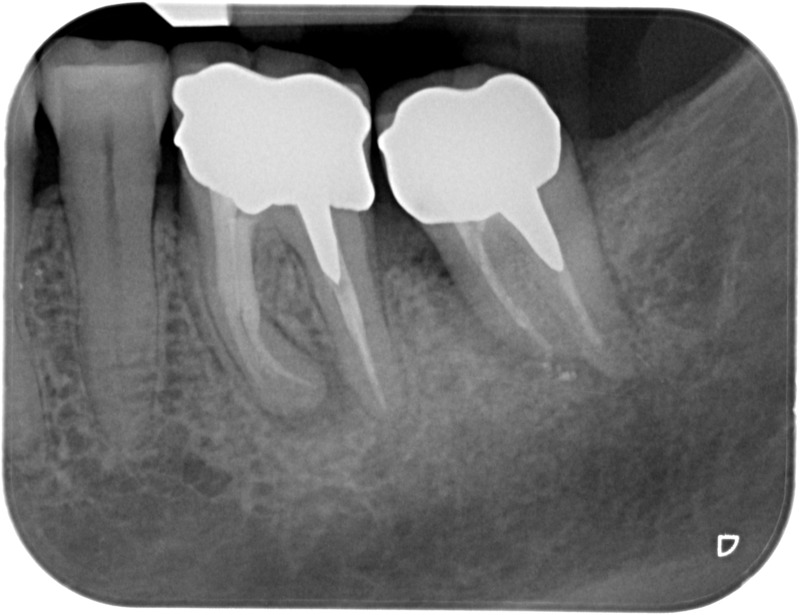

• Couronnes céramiques : Ce sont des prothèses dentaires esthétiques, avec parfois une armature métallique, destinées à rétablir l’anatomie fortement délabrée d’une couronne dentaire naturelle. Une fracture ou une lésion carieuse peut sérieusement endommager une dent qui aura alors besoin d’une couronne périphérique artificielle pour assurer sa conservation. Le soin dit de « dévitalisation » ne prévoit pas systématiquement la protection de la dent par une couronne, l’indication est à évaluer en fonction de la perte de tissu dentaire. De la même manière une dent vivante peut nécessiter la pose d’une couronne céramique sans que nous envisagions de retirer le nerf de ses racines. La couronne « tout céramique », en plus de permettre une reproduction fidèle et esthétique de l’anatomie dentaire, assure un grand confort au patient par sa biocompatibilité.